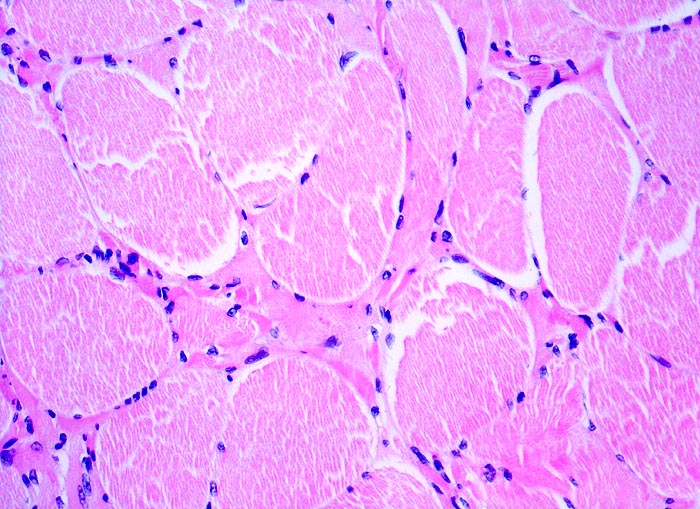

PathoPic – image database / PathoPic ID 5282 - Neurogene Muskelatrophie

Neurogene Muskelatrophie

Hypoplasie/ Involution/ Atrophie

Muskel, quergestreift

Beschreibung

Verletzung des Plexus brachialis bei einem Autounfall. Schwäche der Unterarmmuskulatur.

Histologie

Vergrösserung